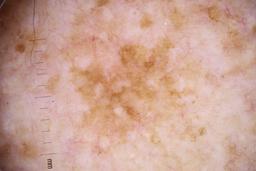

- Name: Challenge 2020: Training

- Number of images: 33,126

- Number of specified lesions: 32,701

- Number of specified patients: 2,056